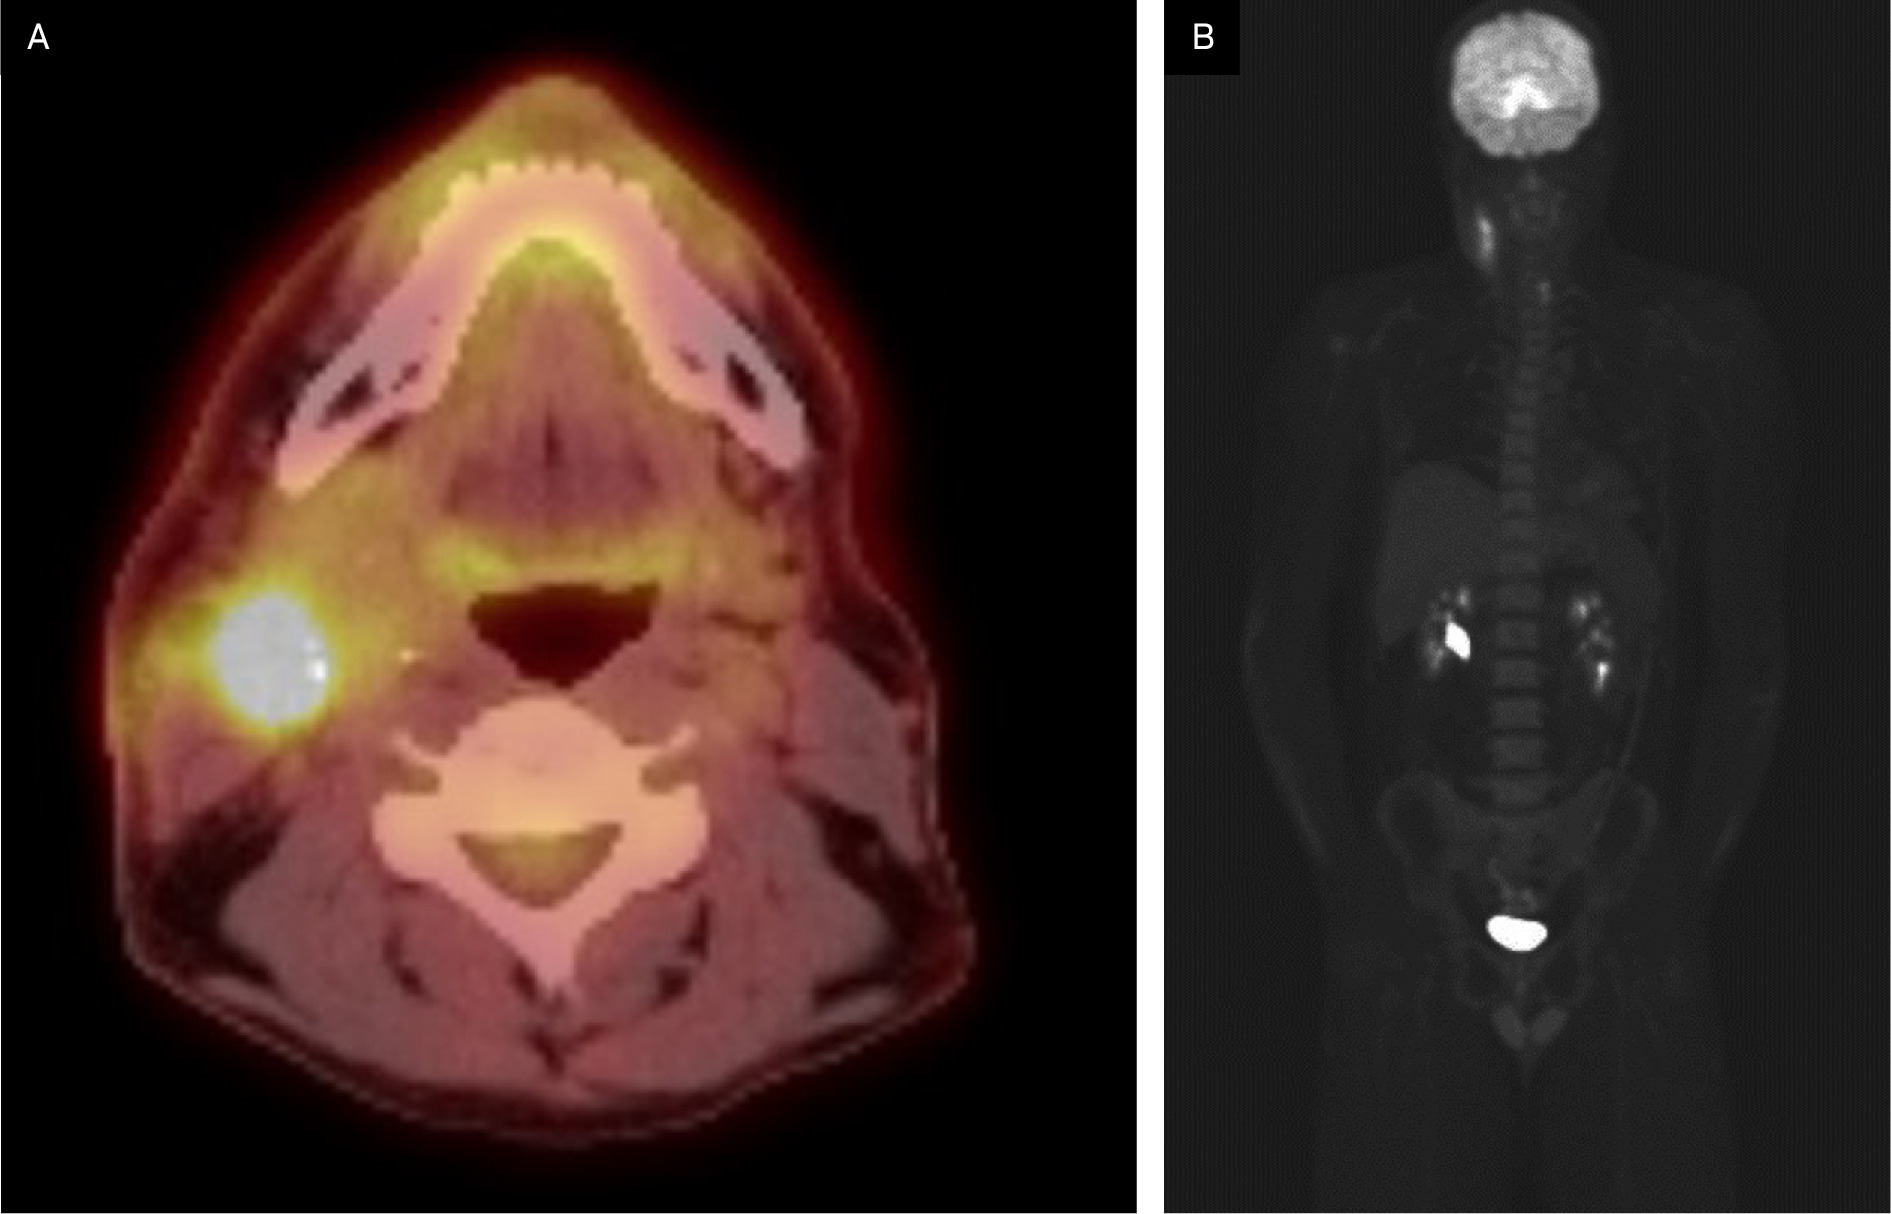

Postoperative PET-CT indicated postsurgical changes in the right upper cervical region with F-18 fluorodeoxyglucose (FDG)-avid, heterogeneous, asymmetric thickening of the anterior aspect of the right sternocleidomastoid muscle and was negative for hypermetabolic lymphadenopathy (Figure 2). There were no findings suspicious for distant metastatic disease.

Key imaging features include enhancement at CT and FDG-avidity at PET-CT. It has also been noted that MMNSTs typically grow along a spinal nerve root with a unique “dumbbell” configuration, though this is a nonspecific finding, as many types of tumors assume this configuration if they contain intradural and extradural components.7-9 MRI is useful in distinguishing them from other tumors, as MMNSTs have intrinsic T1 hyperintensity (Figure 1), while schwannomas and neurofibromas tend to be hypointense on T1 and hyperintense on T2.10